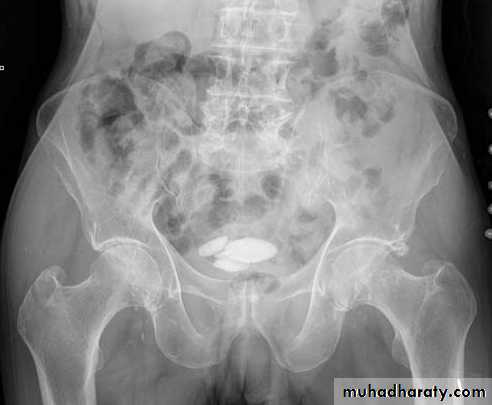

Prostatic calcification

It is so common that can be regarded as normal finding in elderly.It shows no correlation with the patient’s symptoms and does not have any relation to prostatic CA.